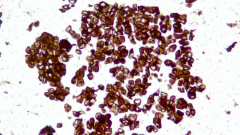

| Description | CLDN18.2是Claudin蛋白質家族的一員,位于細胞膜表面,Claudin18.2(CLDN18.2)表達具有特異性。其作為Claudins蛋白的一個亞型,在正常組織中僅表達于分化的胃黏膜上皮細胞。在胃癌、食管癌和胰腺癌等多種腫瘤中表達,并且不僅限于原發病灶,在轉移灶中也有表達。目前臨床研究中使用的檢測方法均為免疫組化。 |

| 示例 | ![]() |

| IHC染色結果 | |